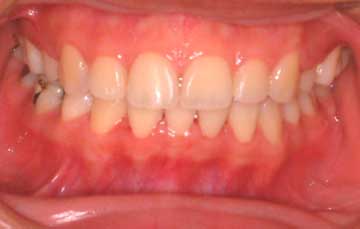

PEDODONTICS – Treatment and proper management of children’s gums & teeth. |